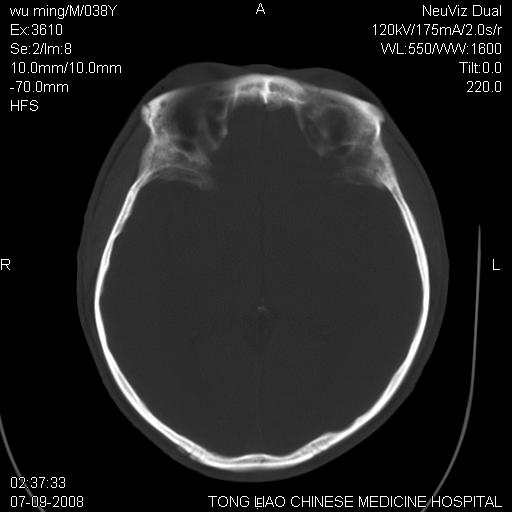

标题: CT14544:患者5楼坠下15分钟后CT扫描,2小时后死亡,请战友指 [打印本页]

标题: CT14544:患者5楼坠下15分钟后CT扫描,2小时后死亡,请战友指

颅底多发骨折。

颅底多发骨折.

颅底多发骨折.上颌骨多发骨折

右侧眼眶,上颌骨,鼻骨、上颌窦等很多

考虑:面骨、颅底骨多发骨折,颅内高压(脑肿胀)。

面骨、颅底骨多发骨折,右侧硬膜下小血肿,弥漫轴索损伤,死亡原因可能是多种因素致。

1)颅底骨及颌面骨多发性骨折。2)副鼻窦及双侧鼻腔积血。

颅底骨折,窦腔内积血。考虑死亡原因为脑水肿压迫脑干或因大量失血死亡。

多发性颅骨骨折

颅底、上颌骨,双侧颧骨多发骨折。死因或许与此无关,是否有腹部脏器损伤有关